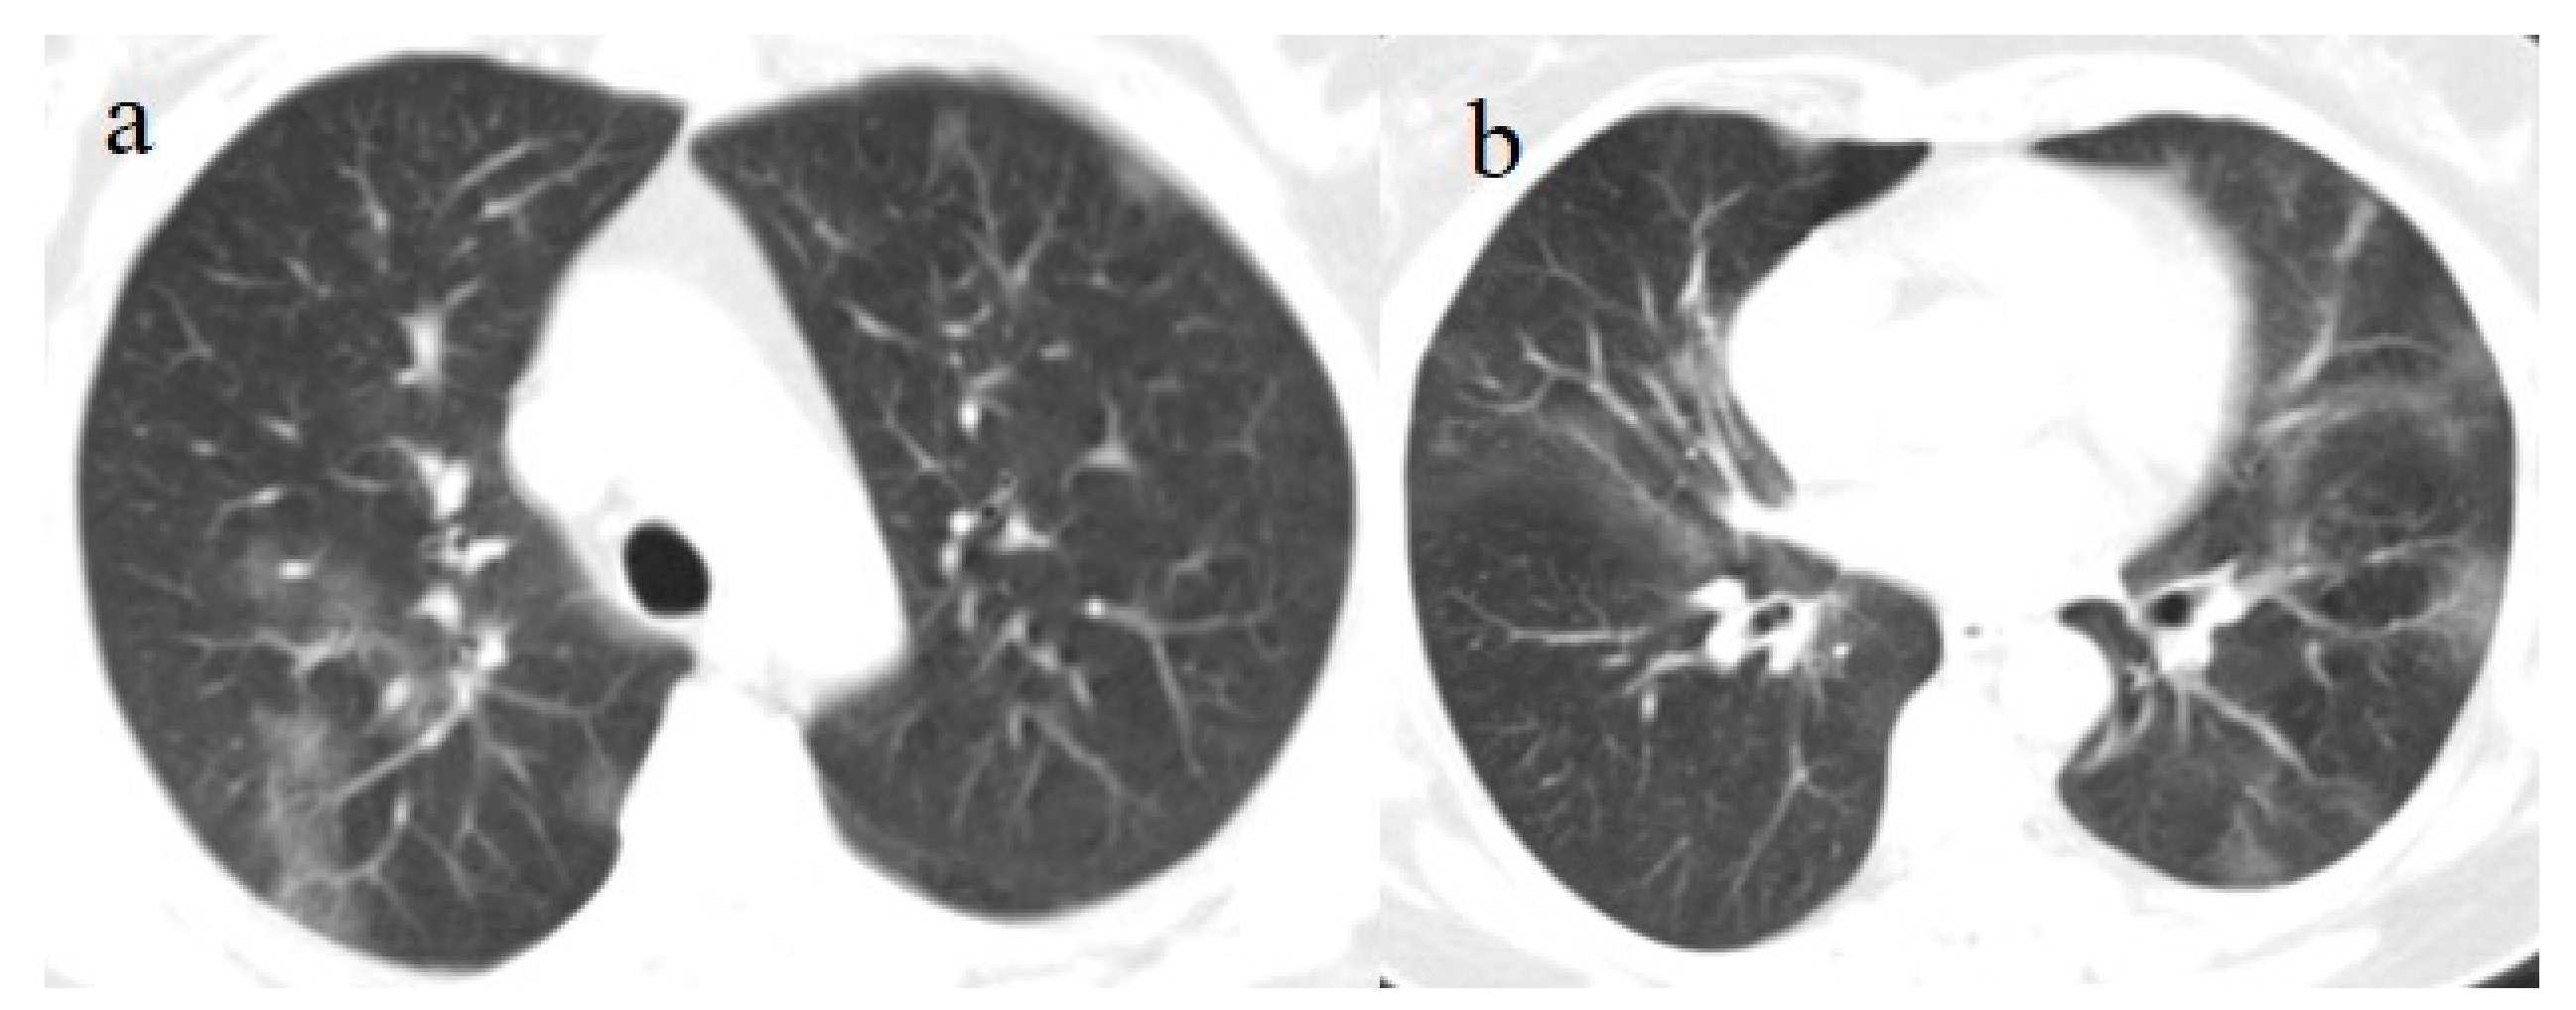

A 53-year-old woman with a history of follicular lymphoma and undergoing treatment with rituximab was fully vaccinated with the COVID-19 mRNA-1273 Pfizer vaccine (first dose on 4 March and second dose on 26 March). About 30 days after vaccination (on 28 April), she tested positive for SARS-CoV-2, and she was also treated with antibody monoclonal therapy. After that, she continued to show three consecutive positive results for SARS-CoV-2 on RT-PCR (on 8, 16, and 20 May) and negative results on 27 May and 21 June. However, on 1 July, she visited the emergency room of our hospital with fever and dyspnea with SO2 at 90%. On admission, she tested positive for SARS-CoV-2 on the NP/OP swab without the detection of any variants. The chest CT showed GGO areas with a peripheral and central distribution and a CT-SS of 11/20 (Figure 5).

Two days after her hospital admission, another OP/NP swab was repeated, which continued to test positive for SARS-CoV-2. However, her clinical conditions improved, and she showed two consecutive negative RT-PCR results on 9 and 13 July. Therefore, the patient was discharged. However, she returned to the emergency room of our hospital on 21 July. She tested positive Sars-CoV-2 on the OP/NP swab performed in the emergency room. The chest CT continued to show GGO, mainly in the inferior lobes with a CT-SS of 9/20 (Figure 6).

Treatment with meropenem (3 g/day given as three doses) and methylprednisolone (1 mg/kg daily for 3 days), followed by prednisone (25 mg once daily with oral administration for 10 days), was prescribed. The patient’s clinical conditions and dyspnea improved. However, she continued to experience fever (38.5 °C) and to test positive for SARS-CoV-2 on the OP/NP swabs on 23, 26, and 3 August with negative results on 11 August and 14 August. Another chest CT has been repeated on 7 August showing new areas of GGO, especially in the superior lobes (Figure 7). Therefore, treatment with immunoglobulin was started with a resolution of some of the previous GGO on the chest CT control made a week later on 14 August. Therefore, the patient has been discharged.

Figure 5. Chest CT performed in the emergency room on 1 July. (a) Some GGO in the left superior lobe, (b) in the right superior lobe, (c) the middle and right lobe, and (d) the inferior lobes.

Figure 6. Chest CT was performed on 21 July. (a) The resolution of some GGO in the superior lobe. However, GGO continued to be present in the inferior lobe, as shown in (b).

Figure 7. Chest CT performed on 7 August (a) showing some new GGO in the superior lobes and also in the middle and inferior lobes (b). On the chest CT performed a week later was visible the resolution of some GGO (c,d).